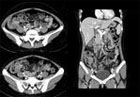

44세 여자 환자로 내원 3주 전부터 발생한 발열 및 1주 전부터 발생한 설사를 주소로 내원하였다. 최근 여행력은 없었으며, 과거력에서 특이 소견은 관찰되지 않았으나, 3주 동안 약 3 kg 정도의 체중 감소를 호소하였다. 이학적 검사에서 혈압 110/70 mmHg, 심박동 94회/분, 체온 38.3 oC 였고, 혈액 검사에서 WBC 2,900/mm3, Hb 11.4 g/dL, platelet count 152,000/mm3 이었고, albumin 3.4 g/dL, AST/ALT 68/49 IU/L, LDH 835 IU/L, CRP 10.1 mg/dL (참고치 < 0.5) 이었다. 복부 전산화 단층 촬영술(그림 1)을 시행하였고, 대장내시경(그림 2)을 시행하였으며, 조직 검사에서 그림 3과 같은 소견이 관찰되었다. 진단은?

Fig. 1 Fig. 2 Fig. 3